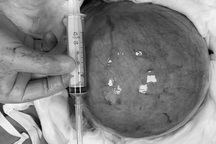

Khối u xơ - cơ tử cung có cân nặng lên tới 2,7kg được bác sĩ bóc tách thành công ra khỏi cơ thể người bệnh

Trong quá trình phẫu thuật, khi mở ổ bụng thám sát, ê kíp phát hiện khối u xơ - cơ tử cung nằm ở vị trí mặt trước tử cung, chỉ đính 1 phần vào thân tử cung nên chỉ bóc tách khối u xơ cơ và khâu phục hồi lại thành cơ tử cung. Khối u được lấy ra khỏi bụng qua đường mổ dài từ khớp mu đến trên rốn 5cm. Sau khi bóc tách, khối u cân nặng lên tới 2,7kg, kích thước tương đương 1 quả dưa hấu có chiều dài gần 30cm. Sau mổ, bệnh nhân phục hồi sớm, vết mổ lành tốt.